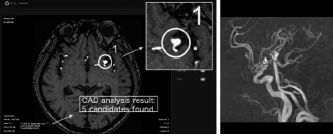

EIRL aneurysmはAI技術を活用し、頭部MR angiography(以下、MRA)画像から未破裂脳動脈瘤と同様の特徴を持つ領域を自動で検出し、その位置を読影者に提示するソフトウェアである(図1)。コンピュータ支援診断computer-aided diagnosis:CAD)の中でも、病変検出を得意とする代物だ。MRA画像がPACSサーバーに取り込まれてから、EIRL aneurysmによる解析が始まり、5分程度で同じ検査の別シリーズとして解析結果が表示される。具体的には、直径2mm以上の脳動脈瘤に類似した候補点を検出し、脳動脈瘤の可能性が高い順番に最大5つの候補点を表示する(図2)。頭部MRA水平断元画像の解析結果の表示画面には、候補点の総数が明示され、丸で囲われた各々の候補点には数字が振られる。たとえば、“1” と番号付けされた候補点は、CADが最も脳動脈瘤らしいと判断した箇所だ。頭部MRAのmaximum intensity projection(以下、MIP)画像にも解析結果を載せることができ、Axial表示かMIP表示、あるいは両方の表示にするかはシステム設定より選択できる。

直径2mm以上の脳動脈瘤に類似した候補点を検出し、脳動脈瘤の可能性が高い順番に最大5つの候補点を表示する。

Axial表示(左)、MIP表示(右)のどちらにも対応可能であり、システム設定により選択できる。

(MIP=maximum intensity projection)

EIRL aneurysmを使用するためには、院内のサーバーにソフトウェアをインストールする必要がある。インストール後に院内PACSと連携され、解析結果がビューワに表示される(図4)。富士フイルムやNOBORI、PSPのビューワにはサービスとして提供され始めており、設置作業費は必要ないが、それ以外のビューワを使用している施設は別途設置作業費(50万円〜)がかかる。表2にEIRL aneurysmの月額使用料金表を示した。毎月の解析検査数により、価格帯は変動する。リモートによる保守作業費用は含まれている。

本製品を使用する際には、CADなしでMRAを読影した後に、CADの解析結果を参照して読影を行う。使用上の注意としては、あくまでEIRL aneurysmの位置付けは医師の読影の補助であり、EIRL aneurysmによる検出結果のみで脳動脈瘤のスクリーニングや確定診断を行うことは目的としていない点である。